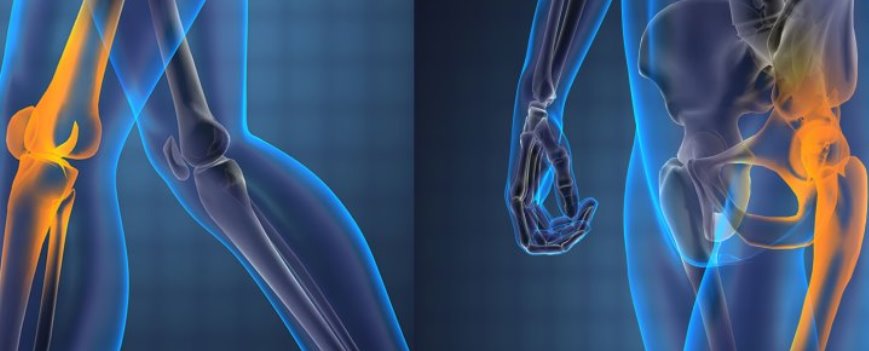

Joint replacement surgeries

Human knee joints are strong. They help in standing, walking, sitting, squatting, cross-legged sitting, jumping and swimming. They are very useful for all kinds of human body moments. But when they bear a lot weight and work too much of time they start degenerating. Initially, the soft tissues in between the bones of a joint which are known as meniscus start degenerating. Then the cartilage. Once the cartilage is lost then the hard bone underneath is exposed and will start degenerating. This exposure and damage increases with work. Then the joint will start bending. Once the degeneration and bending keep on increasing then there will be a change of walking pattern of the patient and the pain will be kept on increasing. This leads to the restriction of joint moments.

But when the joint degeneration is in advanced stage surgery will be the answer. Now in the world, many people are undergoing joint replacements. In England and in the United States of America every year 6 to 7 lakh joints are being replaced.

In our country also nowadays, many people have the awareness of joint replacement surgery and opt for this. Instead of suffering from degenerated joint, instead of walking painfully, instead of not doing any activities, instead of staying only at home- people now start to prefer joint replacement surgery to get back their normal lifestyle. In our hospital for the past seven years we are doing hip and knee joint replacement surgeries successfully.